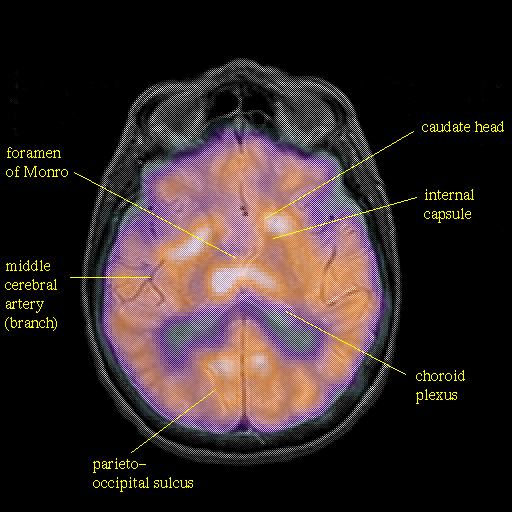

overlay : Slice 29

Slice 29

Pointers

Labeled

[Whole Brain Atlas Home Page] [Brain structure list] [Navigator Help Page]

Keith A. Johnson (keith@bwh.harvard.edu), J. Alex Becker (jabecker@mit.edu)